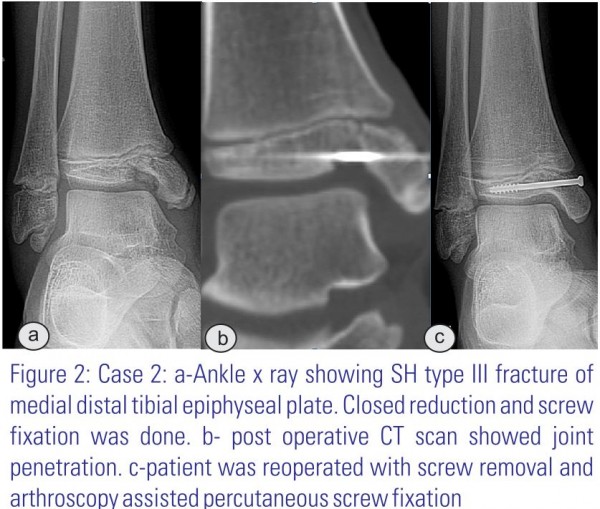

11 year old boy presented with right ankle fracture after fall from a height. X-ray showed a SH type III fracture of the distal medial tibial epiphyseal plate (Fig 2a). This was managed with closed reduction and percutaneous screw fixation. Post operative X-ray showed incongruity of the joint surface. CT scanning illustrated a big impression in the joint surface, through where the screw penetrated and a thin metaphyseal flake on the medial side, confirming that it was a SH type III fracture (Fig 2b). The patient was re-operated after 4 days with removal of the first screw and arthroscopically assisted anatomical reduction of the fracture. The arthroscope was introduced from the anterolateral side and the fracture was reduced using a K-wire as a lever arm. Then a percutaneous screw fixation was performed and arthroscopic pictures were taken peroperatively (Fig 3 a&b). Postoperative X-ray confirmed a good reduction of the fracture and reestablishment of the joint congruity. Postoperatively, the patient was managed with a prefabricated bandage and non weight bearing for 6 weeks. The fracture healed uneventfully, the patient had normal range of motion of the ankle already after 2 months, and the screw was removed after 10 months (Fig 2c). The patient was followed for 16 months, where no complains nor growth disturbance found